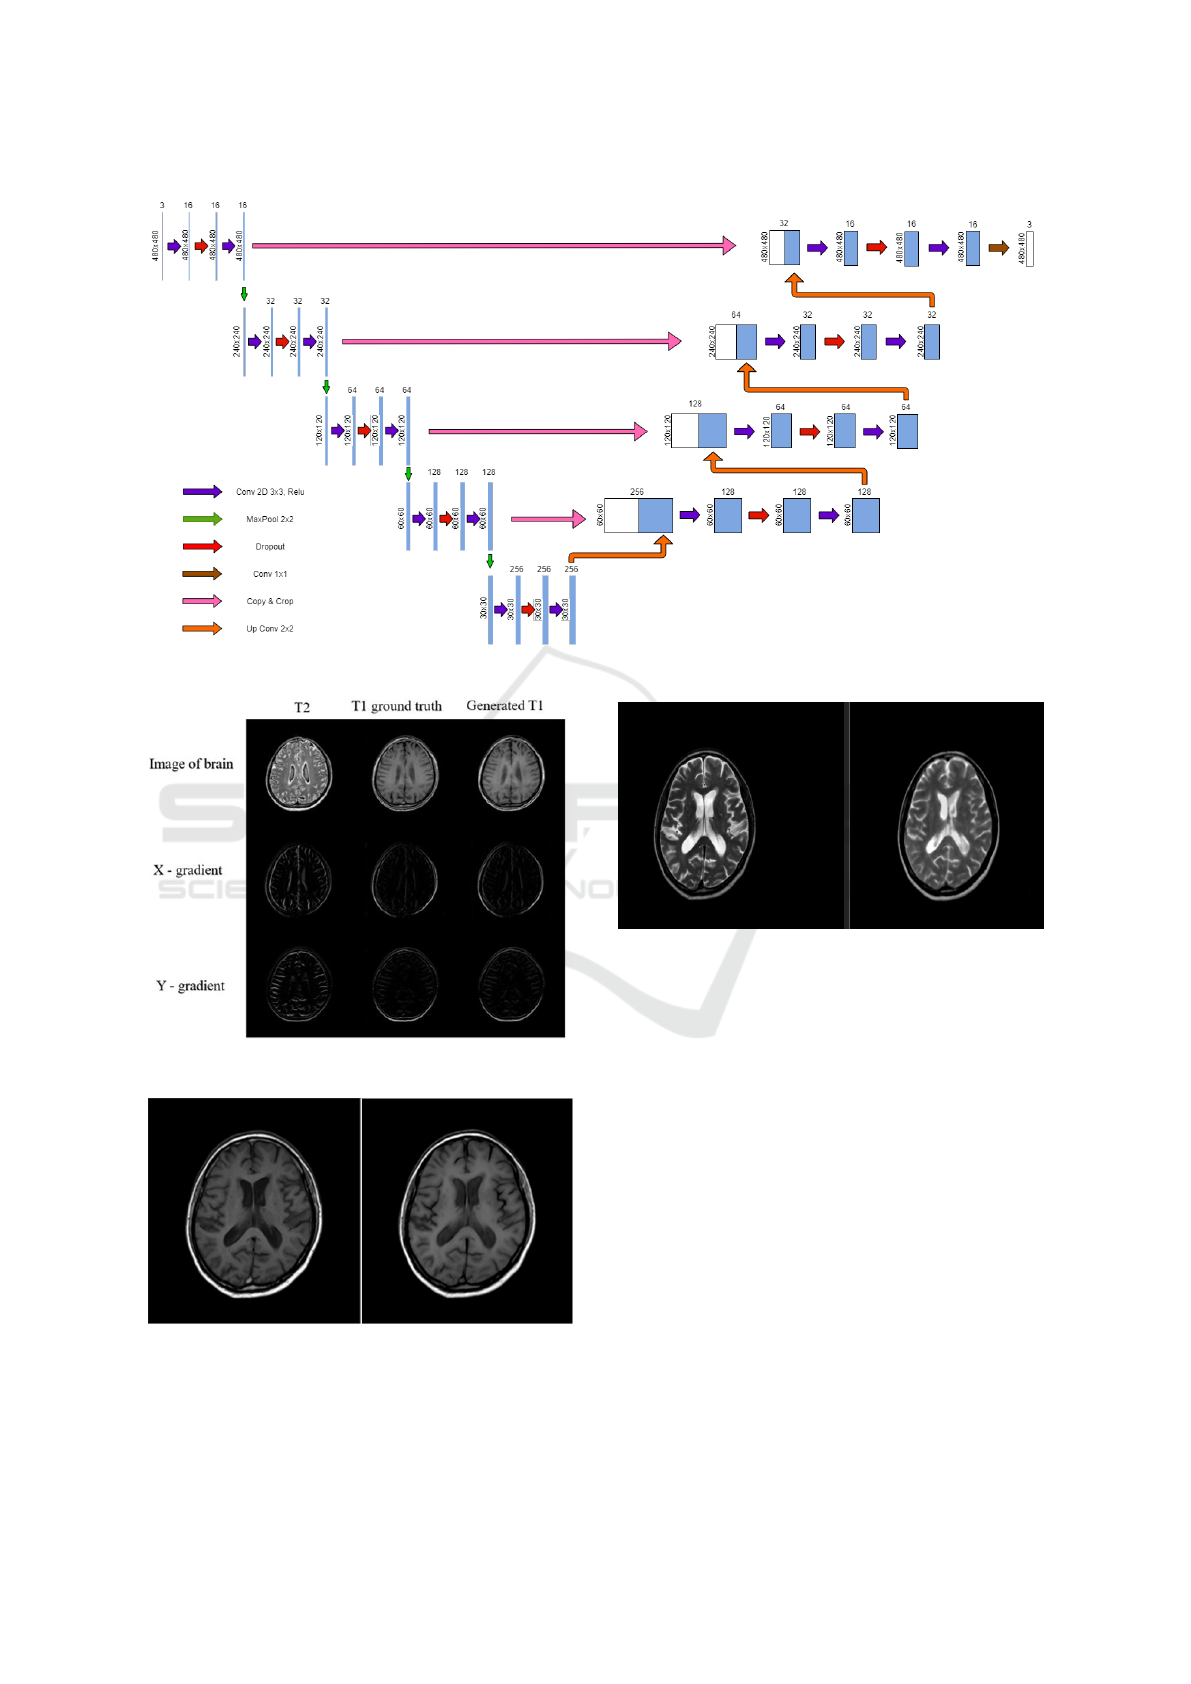

U-Net (Ronneberger et al., 2015) can be consid-

ered as a modified version of encoder decoder archi-

tecture. As shown in Figure 2, U-Net architecture

consists of a contracting path to capture context and a

symmetric expanding path that enables precise local-

ization. The main idea is to supplement a contracting

network by successive layers, where pooling opera-

tors are replaced by up-sampling operators. These

layers increase the resolution of the output. A suc-

cessive convolution layer can then learn to assemble

a more precise output based on this information.

U-Net architecture is divided into 2 parts – a con-

tracting path and an expansive part. As we can see in

Figure 2, in the contracting path, the spatial dimen-

sions are reduced and the number of channels are in-

creased while in the expansive path, dimensions are

increased and channels are decreased. Then, with a

set of transformations, we end up with high-resolution

features which are then combined to predict a relevant